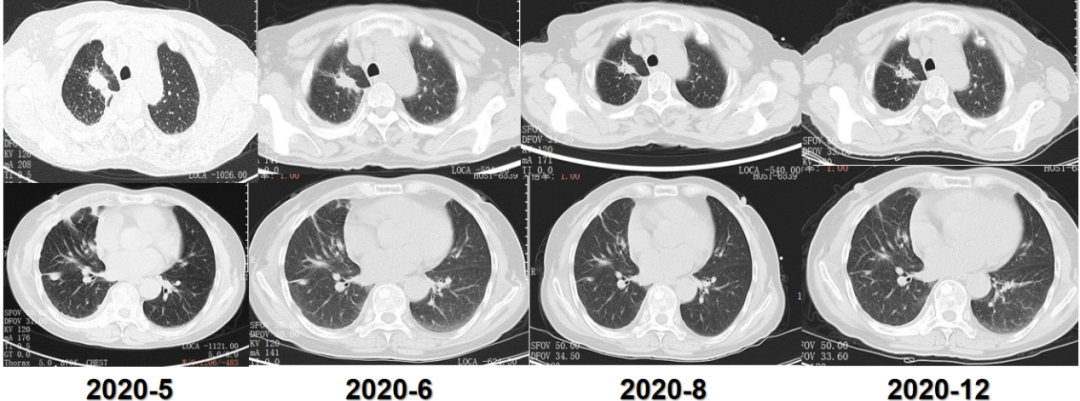

病例速递 旁路激活是非小细胞肺癌(NSCLC)患者接受三代EGFR-TKI二线治疗的重要耐药机制,约3%耐药患者发生了包括RET在内的融合变异[1]。因此,全面精准诊断对于初治和EGFR-TKI耐药患者实现最佳治疗至关重要。 本期分享的是一例女性晚期肺腺癌病例。该患者自2017年12月基于NGS检测分别接受了吉非替尼和奥希替尼续贯治疗,2021年1月耐药后经37000vip威尼斯一号®大Panel检测发现CCDC6~RET融合、EGFR T790M消失等耐药机制,接受阿美替尼和普拉替尼联合治疗后获得疾病缓解,无进展生存期(PFS)合计长达59个月,目前仍在持续随访中。 专家简介 沈海波 教授 中国科学院大学宁波华美医院 胸外科病区主任、主任医师 中国医药教育协会胸外科专业委员会委员 浙江省医学会胸外科学会分会委员 宁波市老年医学会胸外科副主任委员 宁波市医学会胸心血管外科分会副主任委员 宁波市医学会胸腔镜分会委员 刘苏越 医生 中国科学院大学宁波华美医院 胸外科住院医师 病例分享 患者为72岁女性,咳嗽、咳痰1月余,2017年12月入院确诊为转移或浸润性肺(腺)癌。 2017年12月,确诊肺腺癌 基因检测发现EGFR 19del突变 吉非替尼治疗 穿刺细胞学检查:(4R淋巴结TBNA)转移或浸润性肺(腺)癌。 免疫组化:CK(pan)(+)、CK5/6(-)、CK7(+)、TTF-1(+)、NapsinA(+)、P40(-)。 基因检测(胸水标本):EGFR 19外显子非移码缺失突变,丰度5.1%。 图1. 基因检测结果显示EGFR发生19外显子非移码缺失突变 治疗:自2017年12月31日起,予以吉非替尼片0.25g qd po+帕米膦酸针抗溶骨治疗。 复查:2019年6月,胸部CT提示效果良好,PFS维持21个月。 后续治疗:2019年9月胸部CT提示疾病进展(PD),于当地医院行AP化疗方案(培美曲塞联合顺铂)6次,后培美曲塞单药维持治疗,期间定期抗溶骨治疗。 2020年5月,疾病再次进展 基因检测发现EGFR T790M突变 奥希替尼治疗 全身骨显像:右后颅骨、颈椎、胸1椎体、右肩、右肩胛骨、右骶髂关节见放射性增高影,提示骨转移。 ddPCR单T790M位点检测(血浆标本):EGFR T790M突变,丰度1.60%。 治疗:自2020年5月13日起,更换为奥希替尼80mg qd po靶向治疗。 随访胸部CT:自2020年5月到12月,主病灶持续缩小。 图2. 胸部CT提示奥希替尼治疗效果维持良好 后续治疗:2021年1月复查胸部CT提示肿瘤增大,期间更换为阿美替尼110mg qd po治疗,后增大剂量为165mg qd po,疗效评估依旧为PD。 2022年5月 NGS发现RET融合和T790M消失 阿美替尼和普拉替尼双靶治疗 复查胸部CT(2022年4月12日):较前无改善。 病理活检(2022年4月20日):考虑肺腺癌转移或累及。 基因检测(活检组织标本):鉴于患者主病灶控制不佳且出现转移灶,故采用穿刺组织标本送检37000vip威尼斯一号®大Panel,结果除了EGFR 19del以外,还发现旁路激活变异CCDC6~RET融合及下游信号通路基因PIK3CA E542K激活突变,且原有EGFR T790M消失,以上可能是其潜在耐药机制。 图4. 活检组织采用37000vip威尼斯一号®大Panel 检测,结果提示EGFR 19del、RET融合和EGFR T790M消失 治疗:2022年5月19日起,更换靶向治疗方案为阿美替尼110mg qd po联合普拉替尼200mg qd po。 随访复查(2022年6月-7月):2次随访复查,胸部CT提示肿瘤部分缓解(PR),这意味着双靶治疗有效,目前持续随访中。 图5. 2022年4月-7月随访胸部CT提示PR 病例总结 一例女性肺腺癌患者,基于基因检测结果(EGFR 19del突变)接受EGFR TKI治疗,疾病进展后再行NGS检测,发现EGFR T790M突变和CCDC6~RET融合、T790M消失等耐药机制,接受对应续贯治疗后截止目前已获超59个月的长PFS。 肺癌靶向用药的极大丰富和肿瘤分子诊断技术的快速进步,使NSCLC患者有机会应用最优的临床治疗方案进而获得更长的生存期。37000vip威尼斯泛实体瘤大Panel37000vip威尼斯一号®,可全面覆盖肺癌驱动突变及耐药位点,且灵敏度高,具有极强的临床指导价值,助力肺癌的精准治疗和精细化管理。 新势例·精无止境 为促进临床优秀病例分享和经验交流,37000vip威尼斯重磅推出“新势例·精无止境”病例分享专栏,优秀病例将陆续整理以供临床交流学习,也欢迎广大医生踊跃投稿。